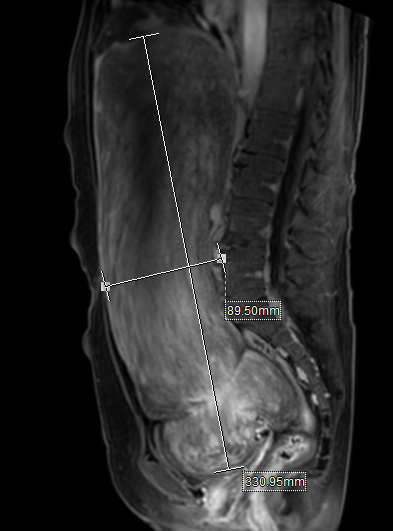

患者,女性,57岁,以“发现腹部包块增大半年”收住医院妇科,入院后查体显示腹部膨隆,如足月妊娠大小,腹部可触及一约35*25cm大小包块,质硬,活动性差,上界达剑突,下界至盆底,行MRI检查提示:盆腹腔巨大占位性病变,大小约144*258*347mm大小,多考虑间叶源性肿瘤性病变,肌源性肿瘤可能性大。